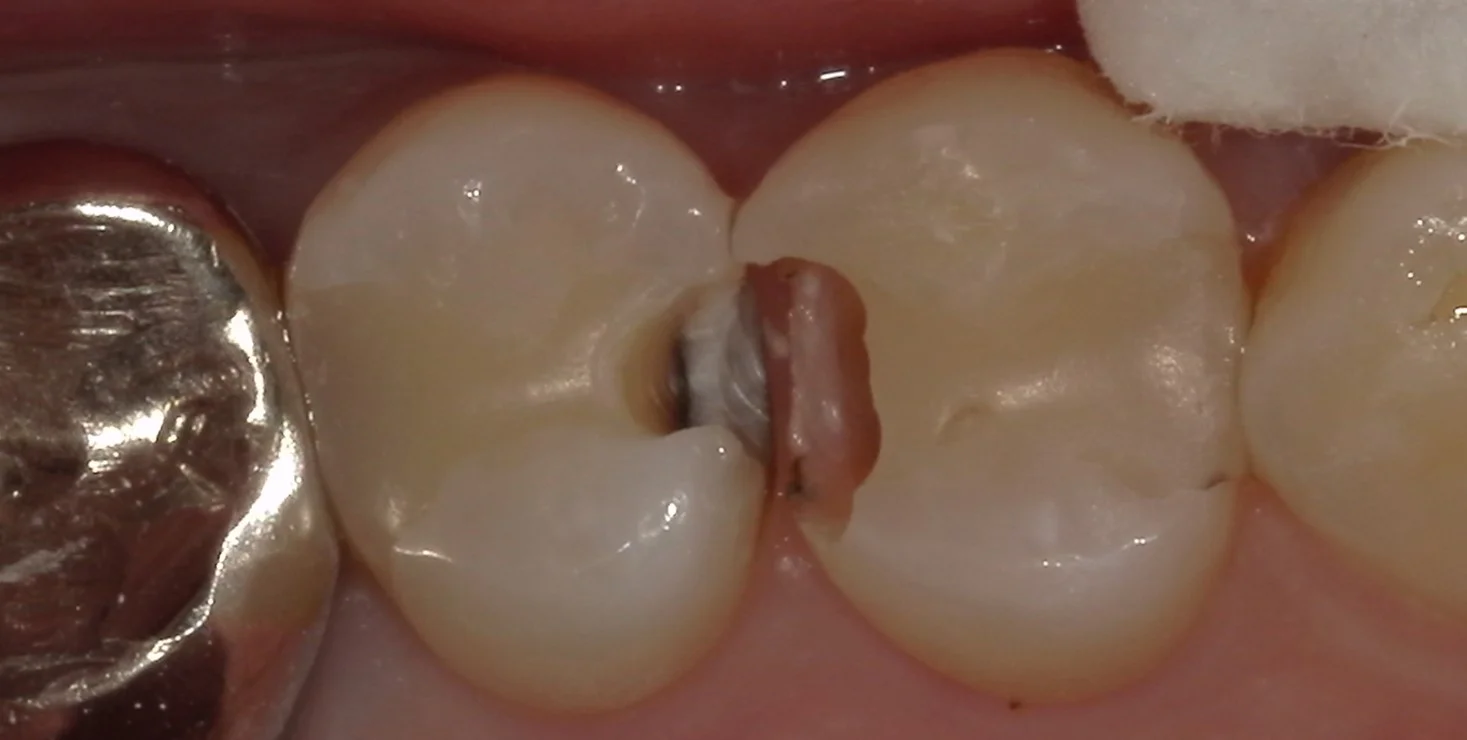

軽く虫歯を見やすくしたのがこちらです。

白い部分がエナメル質といって人間の体の中で最も硬い構造になります。

そこを超えて大きく中に虫歯が入り込んでいるのが分かるかと思います。

基本的に私はこの象牙質の1/3を超えた虫歯については治療が必要と判断していますが、今回は大幅に超えていたので、様子見ではなく治療介入としました。

ちなみに、コンポジットレジンもダイレクトボンディングも使用している材料自体の物性は一緒ですので、メリットの部分でも記載している通り、例えばこういった感じで虫歯になった部分だけ取り除いて詰めなおす「補修修復」というものが理論上は可能となっています。

ただし元々詰めているレジンに新しく詰めるレジンを接着させるというのは実は非常に難しいです。

また今回は元々詰めていたコンポジットレジン自体の劣化も激しいので、完全に取りきってやり直すこととしました。